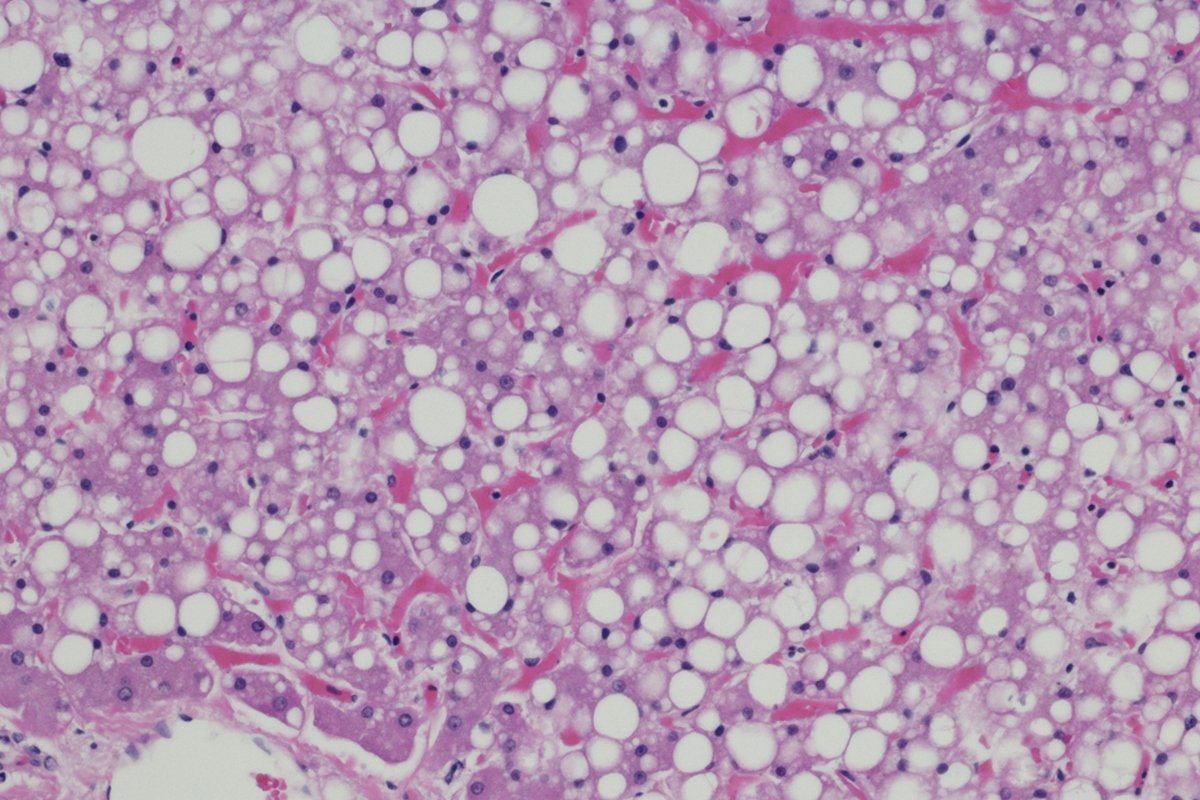

Uma condição cada vez mais comum, a esteatose hepática, conhecida como gordura no fígado, é uma doença de estilo de vida. Desencadeado por obesidade, má alimentação, sedentarismo e excesso de álcool, o acúmulo excessivo de gordura nas células hepáticas é preocupante e pode causar problemas sérios de saúde, como cirrose e até câncer.

O gastroenterologista e hepatologista Rodrigo Rêgo Barros conta que o diagnóstico precoce é fundamental. “A esteatose hepática é uma condição reversível quando diagnosticada precocemente. Com uma alimentação equilibrada, prática regular de exercícios e controle do peso corporal, o fígado tende a se regenerar e eliminar o excesso de gordura”, afirma o médico.